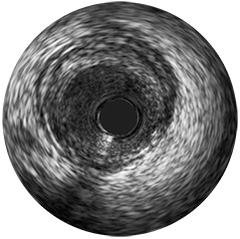

Einführung der völlig neue Anwendungsplattform IntraSight von Philips – Zusammenspiel von Bildverarbeitung, Physiologie, Koregistrierung und Software für eine optimale Patientenversorgung. IntraSight bietet eine umfassende Palette klinisch bewährter Modalitäten wie iFR/FFR, IVUS und Koregistrierung* für einfachere komplexe Interventionen, schnellere Routineverfahren und eine verbesserte Patientenversorgung.

IntraSight ist auf Basis einer intelligenten, anwendungsbasierten Plattform konzipiert, die sich bei neuen verfügbaren Anwendungen und Modalitäten an die sich ändernden Anforderungen Ihres Labors anpassen lässt – und das ohne neue Hardware erwerben zu müssen. Nur IntraSight von Philips bietet Ihnen erstklassige Bildverarbeitungs- und Physiologie-Tools mit iFR, iFR-Koregistrierung*, FFR, IVUS, IVUS-Koregistrierung* und Angio+*. Dank seiner modularen Architektur bleibt IntraSight über die neuesten Entwicklungen und wichtigen Sicherheitsupdates auf dem Laufenden.

Digitale IVUS- Bildverarbeitung

Mit IntraSight wird die Laborleistung durch Touchscreen-Steuerung am Untersuchungstisch, Systemintegration, Datenverwaltung und Ferndiagnose von Diensten optimiert